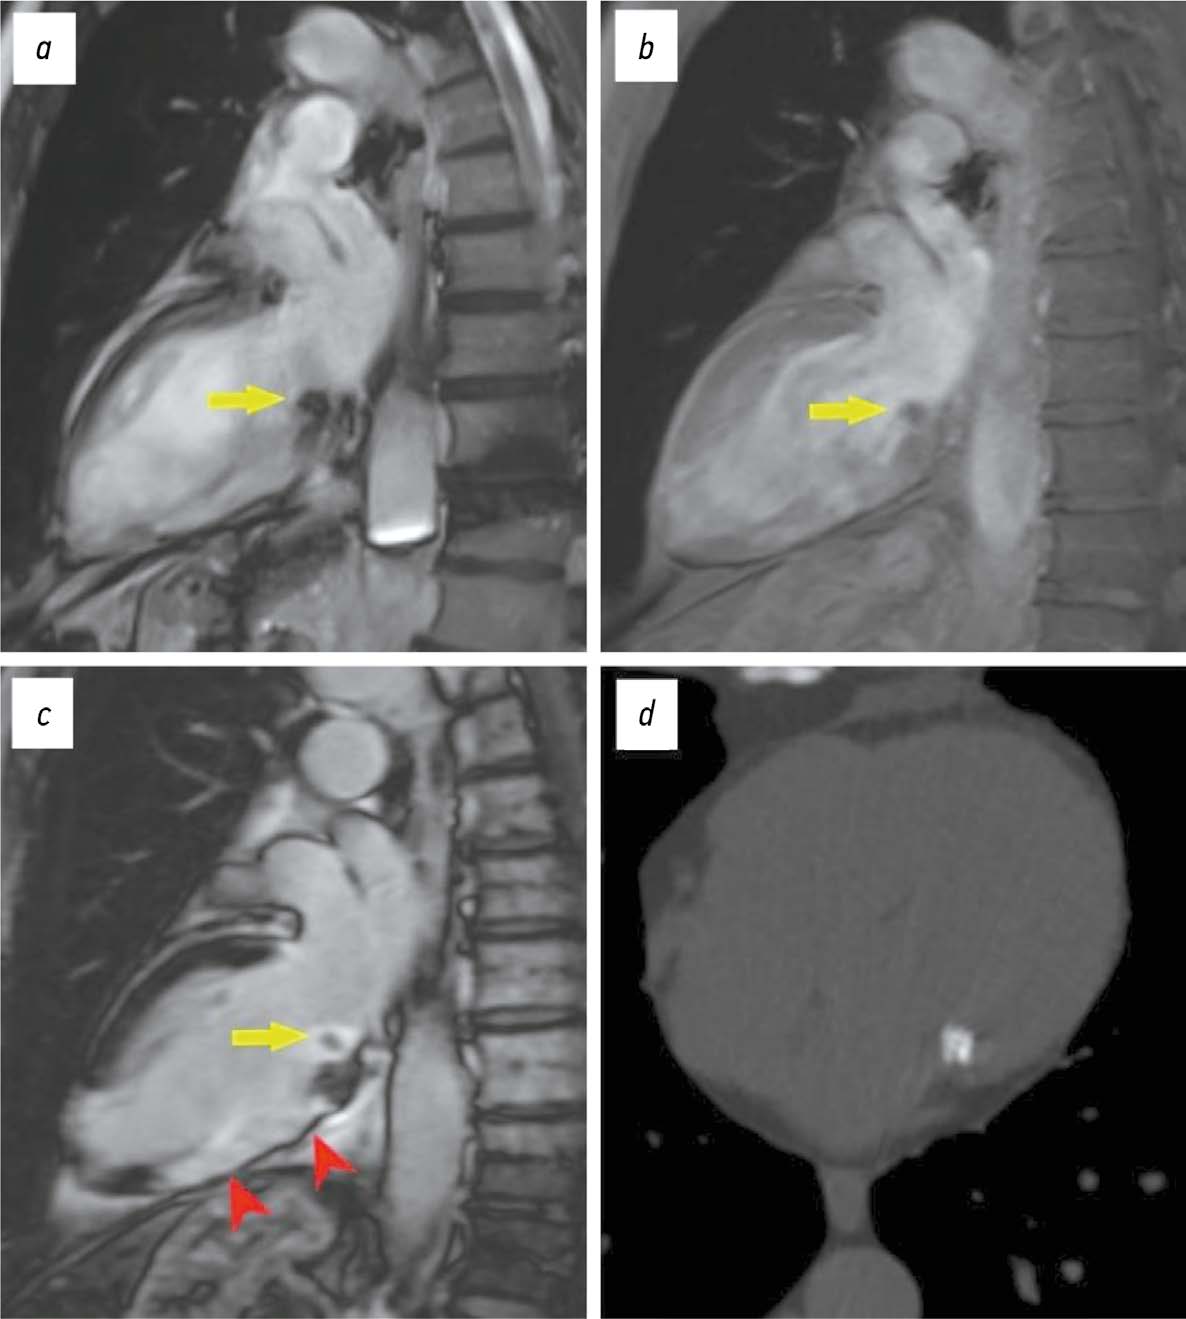

Magnetic resonance imaging in diagnosis of serous adenocarcinoma of fallopian tubes: a case report

Abstract

Serous adenocarcinoma of fallopian tubes is an extremely rare and difficult to diagnose type of cancer of the female reproductive system. This condition is often asymptomatic or has a non specific clinical presentation including serosanguineous vaginal discharge and colic like pain in the lower abdomen and pelvis. These symptoms are reported in the literature as the Latzko’s triad and are considered pathognomonic for tubal cancer, but their combination is observed in less than 15% of patients. The low incidence and lack of the pathognomonic clinical presentation lead to many diagnostic errors or detection of advanced disease, which significantly worsens the patient’s prognosis. An accurate surgical diagnosis is made in only 4% of cases. This case report describes serous adenocarcinoma of fallopian tubes with all signs of the Latzko’s triad and MRI suggestive of serous adenocarcinoma of fallopian tubes at a preoperative stage.

882-892